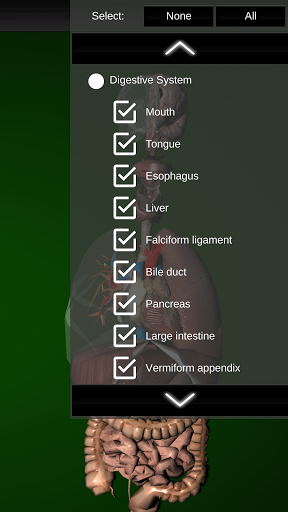

* Spijsverteringsstelsel, inclusief de maag, dunne darm, dikke darm, en een animatie van dit systeem.